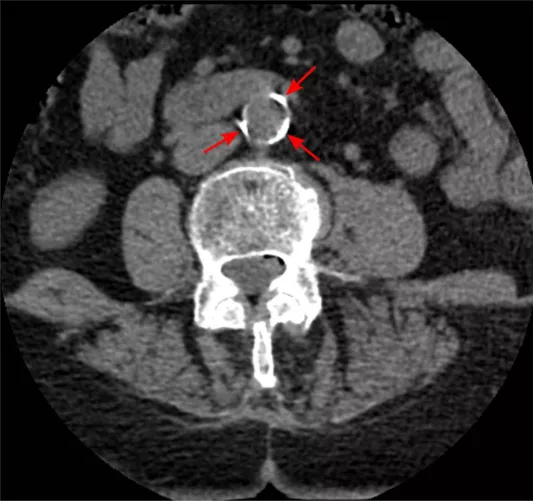

CT-felvétel meszes hasi aortåról

A csigolya elƑtt lĂĄthatĂł hasi aorta (nyilakkal jelezve) "vilĂĄgĂ­t" az elmeszesedĂ©s miatt – CT rĂ©tegfelvĂ©tel, szerzƑ: Jmarchn, liszensz: CC BY-SA 3.0 (Wikimedia Commons)